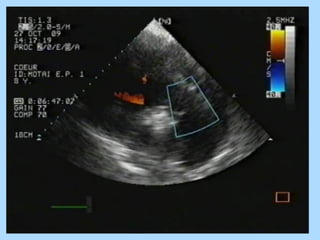

Дигоксин - это лекарство, относящееся к группе сильнодействующих веществ, которые называются сердечными гликозидами . Сердечные гликозиды - это особые вещества растительного происхождения, которые могут действовать на сердечную мышцу, в результате чего улучшается ее тонус и работа сердца в целом .

Дозировка анаприлина при аритмии: по 1 - 2 таблетки по 10 мг 3 — 4 раза в день; максимальная суточная доза - 120 мг, то есть 12 таблеток . При внутривенном введении используется доза 0,1 мг/кг . Препарат вводится в течение 15 минут под контролем давления . Анаприлин при мерцательной аритмии обычно назначается вместе с дигоксином .